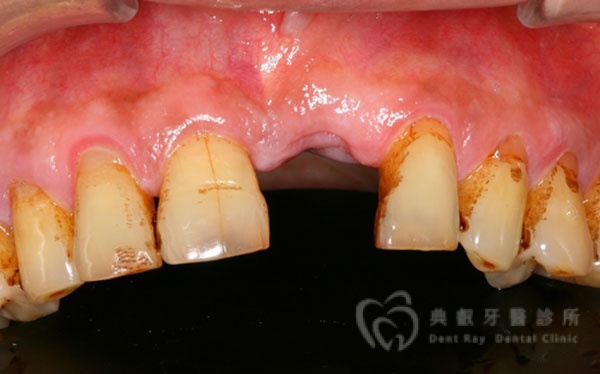

植牙案例四

植牙案例